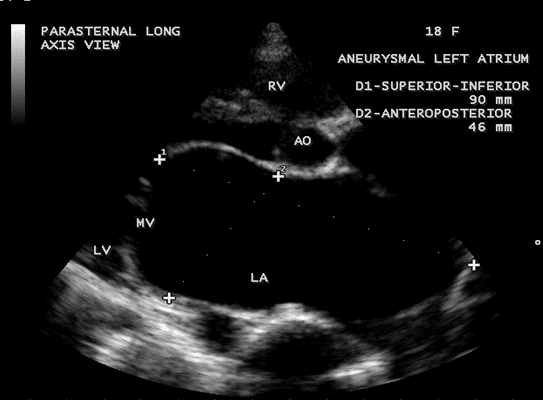

Case 3. Aneurysmal left atrium in a 18 –year old girl due to isolated severe rheumatic mitral regurgitation as shown in Figures 9 to 14. The patient was presented with stroke and treated with anticoagulants and antiplatelet agents and, advised lifelong penicillin prophylaxis and MVR (mitral valve replacement).

Figure 11. Parasternal long axis view showing the aneurysmal left atrium in a 18-year old girl due to pure rheumatic mitral regurgitation

Figure 12. Parasternal long axis view showing the severe mitral regurgitation touching the entire length of dilated left atrium and the length of jet is correlating with superior-inferior dimension of the left atrium in an 18-year-old girl

Echocardiography is an excellent, non-invasive technique for obtaining anatomical measurements and it is universally accepted to asses the left atrial size [42], comparable to angiography. Since the left atrium is not a symmetrically shaped 3D structure, the linear dimensions inaccurately represent the LA size, widely used in clinical practice and shown to correlate with angiographic measurements. Expansion of the left atrium in the AP (anteroposterior) dimensions may be constrained by the thoracic cavity between the sternum and the spine. Predominant enlargement in the superior-inferior and medial-lateral dimensions will alter the LA geometry and the AP dimensions also may not be representative of LA size [43]. Kawazoe, et al proposed two echocardiographic criteria to define the giant left atrium [44].

- Large left atrium depicted by M-mode echocardiography with diameter > 65 mm

- Left ventricular posterobasal wall bent inward and lying between the dilated LA cavity and LV cavity. The length of postero-basal part of LV compressed by large LA ≥ 30 mm was defined as ‘ giant left atrium’ [45] as shown in Figure 17.

Cross sectional echocardiography is superior to M-mode echocardiography for measuring left atrial size [46],[47] and it allows the visualization of entire left atrium from different views [48]. The presence and extent of chamber dilatation could not be predicted by the use of a single dimension. In normal subjects, the SI (superior-inferior) dimension being the major axis and the ML (medial-lateral), AP (anteroposterior) dimensions are the minor axes, and the SI dimension is usually the largest among the left atrial diameters and it should include the measurements of all three dimensions to determine the presence and to measure the degree of LA dilatation.

The extreme dilatation of the left atrium is probably related to the jet of regurgitation (or insufficiency), a finding common to all as shown in Figure 12, the jet occupies the entire left atrium as in Figure 13 and a holosystolic pattern in color M-mode echocardiography as shown in Figure 14.